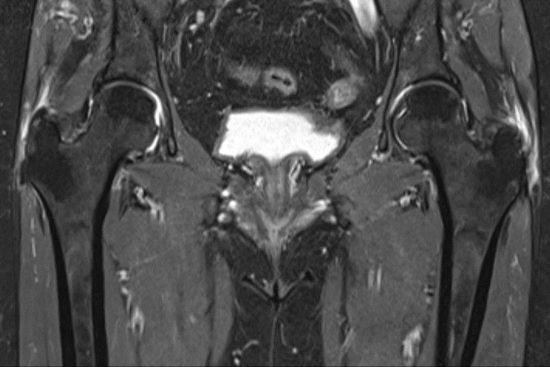

La trocanteritis, también conocida como bursitis trocantérea, es una inflamación de las bursas —pequeñas bolsas llenas de líquido— que se encuentran alrededor del trocánter mayor del fémur. Aunque puede afectar a cualquier persona, es especialmente común en mujeres a partir de los 40 años, corredores y personas que pasan muchas horas de pie o con sobrepeso.

El síntoma más característico es un dolor en la cara lateral de la cadera, que empeora al caminar, subir escaleras o tumbarse de lado. Muchas veces, este dolor se confunde con una patología lumbar, con artrosis de cadera o incluso con problemas musculares, lo que retrasa un diagnóstico certero.

Como explica el Dr. Valero, “cuando la inflamación de la bursa se vuelve crónica o se asocia a lesiones tendinosas, es fundamental realizar un diagnóstico preciso con pruebas de imagen avanzadas y considerar opciones quirúrgicas mínimamente invasivas”.

La artroscopia de cadera permite tratar directamente la causa del dolor —ya sean bursas inflamadas, calcificaciones o fricciones con tendones glúteos— con incisiones mínimas y una recuperación rápida.